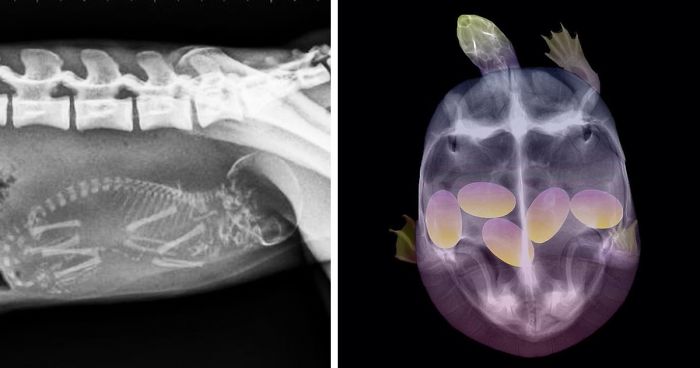

X-Ray Of A Pregnant Turtle

This is my image!! Follow me on instagram @taz_photo_ . Working on putting a website together :)

It came in missing it's front leg! We don;t know why.

Load More Replies...An X-Ray Of A Pregnant Francois Langur Monkey

We Just Found Out That One Of Our Transmitted Tortoises Is Pregnant